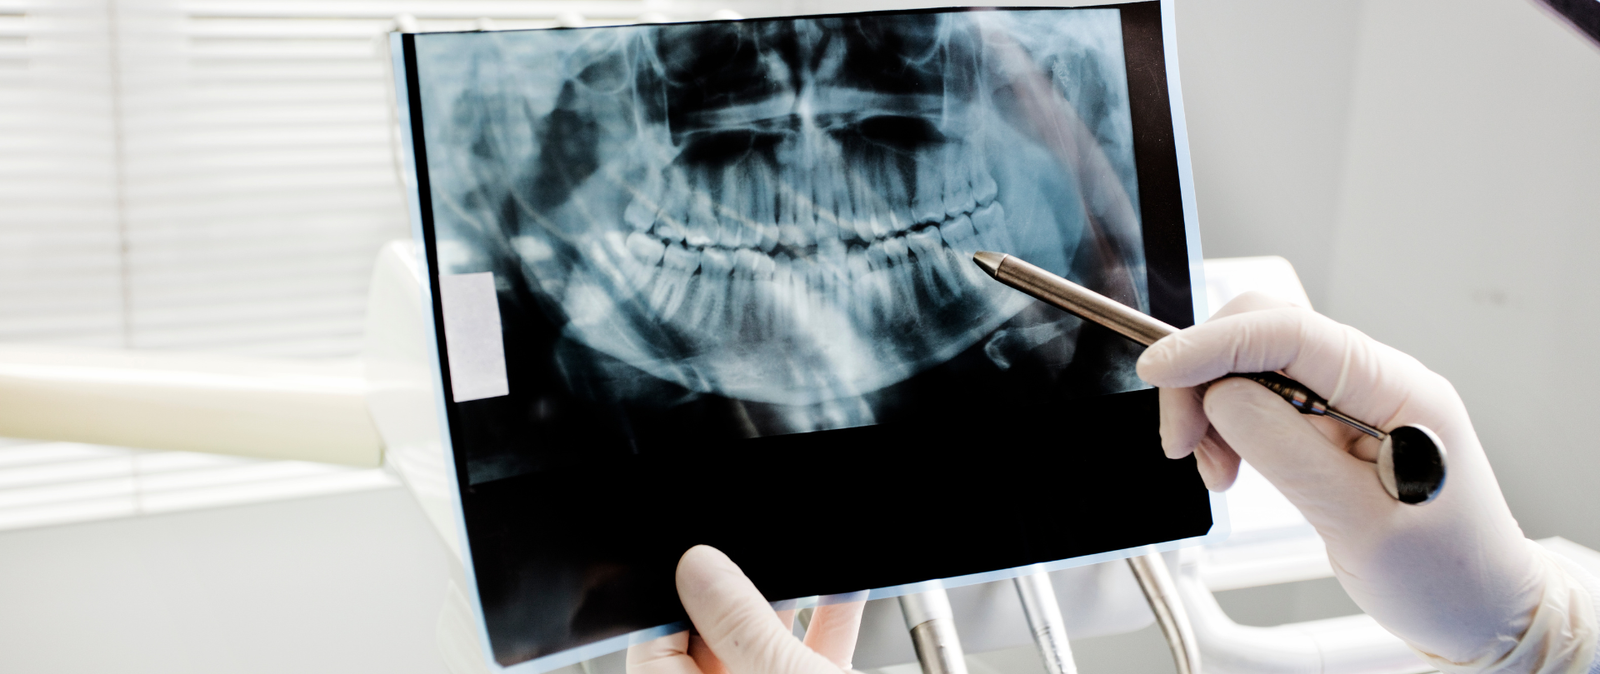

Η ακτινοδιάγνωση είναι ο επιστημονικός κλάδος της οδοντιατρικής που ασχολείται με τη λήψη και ερμηνεία διαγνωστικών απεικονίσεων των δοντιών, των γνάθων και της στοματικής κοιλότητας. Στο σύγχρονο οδοντιατρείο μας στην Αθήνα, χρησιμοποιούμε προηγμένα συστήματα ψηφιακής ακτινογραφίας, επιτρέποντας στους ειδικούς να διαγνώσουν με ακρίβεια παθήσεις που δεν είναι ορατές με γυμνό μάτι.

Με την ψηφιακή ακτινογραφία, τα αποτελέσματα είναι άμεσα διαθέσιμα. Ο οδοντίατρος μπορεί να τα αξιολογήσει επιτόπου και να συζητήσει μαζί σας το πλάνο θεραπείας.